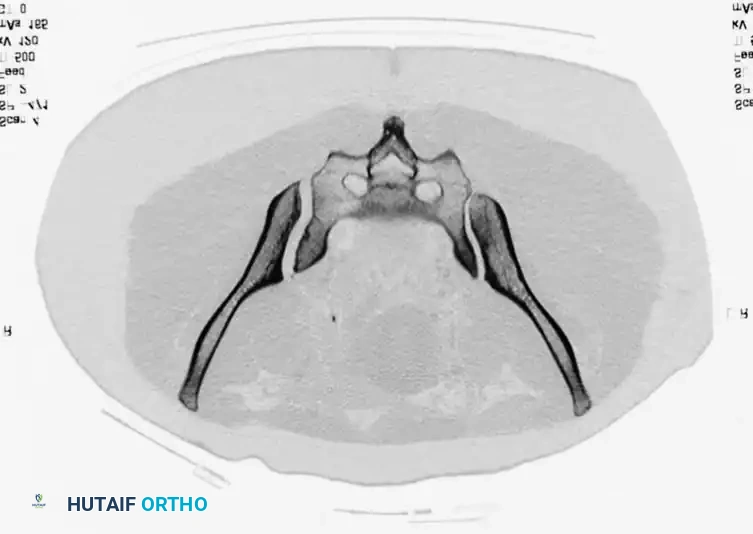

• CT Scan: The gold standard for evaluating posterior ring injuries, sacral dysmorphism, and preoperative planning for percutaneous fixation.

3. Percutaneous Sacroiliac (SI) Screws (Posterior Ring)

The gold standard for posterior ring fixation in appropriately selected patients.

* Indications: Sacral fractures, SI joint disruptions, crescent fractures.

* Technique: Performed under strict fluoroscopic guidance (Inlet, Outlet, and Lateral sacral views).

* Trajectory: The guide wire is advanced from the lateral ilium, across the SI joint, into the S1 (or S2) vertebral body.

* Safety Corridors: The surgeon must possess an intimate understanding of sacral dysmorphism. The "safe zone" is bounded by the sacral neural foramina inferiorly, the spinal canal posteriorly, and the sacral ala anteriorly.

Pitfall: Failure to recognize a dysmorphic sacrum (characterized by upper sacral segment elevation, non-recessed alae, and oblique neural foramina) can lead to catastrophic L5 nerve root injury or vascular penetration during SI screw placement.